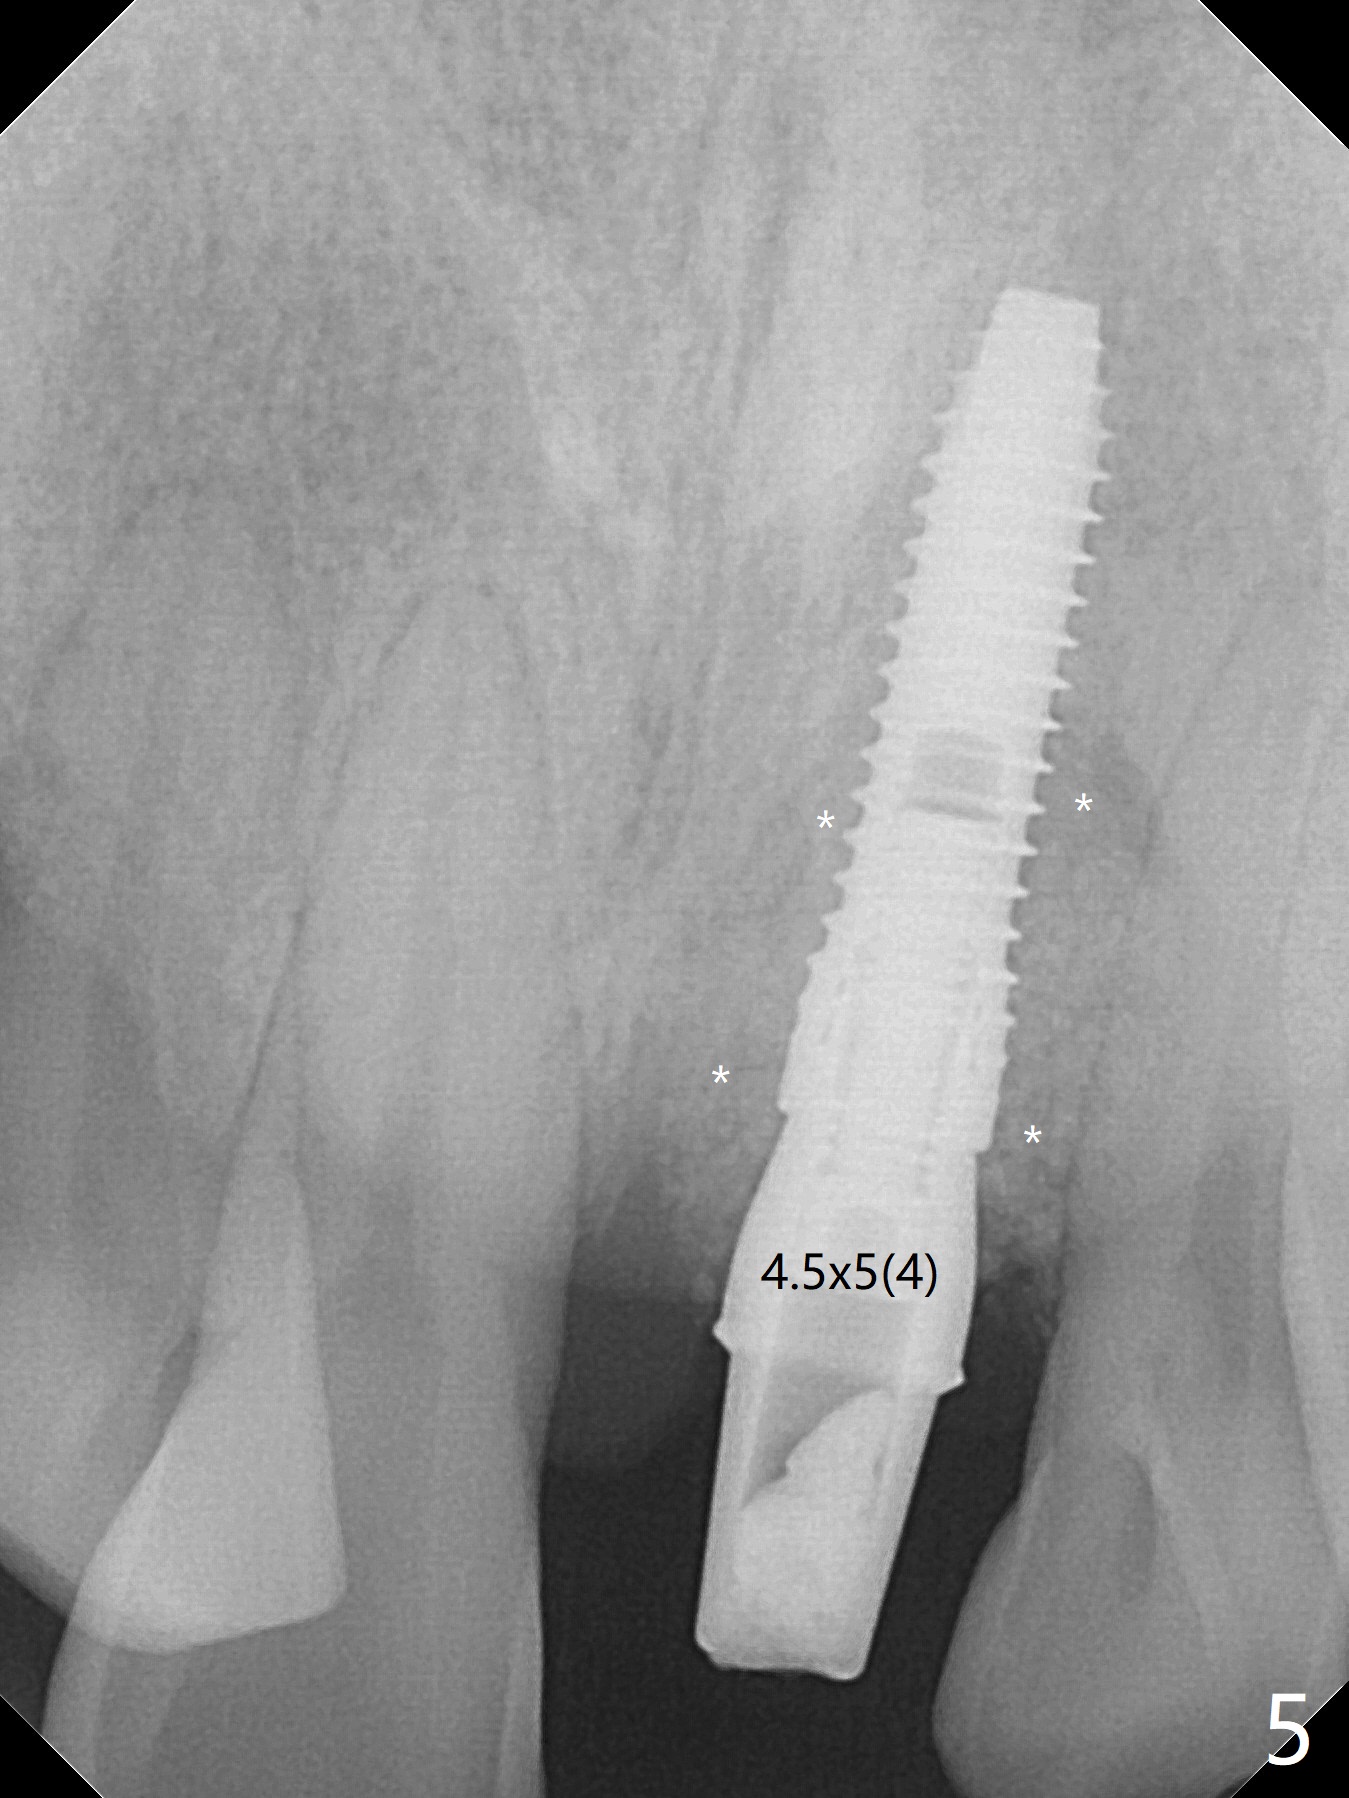

Immediately preop PA confirms loss of the buccal plate at #9 (Fig.1 *). In contrast the palatal crest is ~ 4 mm subgingival (WNL) after extraction. When initial osteotomy reaches 18 mm, there is moderate hemorrhage, probably due to close to the nasal floor (Fig.2 red dashed line). Following sequential osteotomy, a 3.8x15 mm dummy implant is placed partially (Fig.3 (pink: apical osteotomy)). After placement of an implant with the same dimension as the dummy's (Fig.4), PRF is laid against the inner surface of the buccal defect and allograft (Fig.5 *) is packed mainly in the buccal gap before and after insertion of a 4.5x5(4) mm abutment. The patient is satisfied with the immediate provisional (Fig.6: 1 week postop). The buccal margin of the provisional is shortened with exposure of bone graft to facilitate gingival downgrowth (Fig.6: 1 month postop). The buccal plate seems to collapse nearly 2 months postop (Fig.8 *), probably due to loss of the bone graft. The abutment is exposed buccally (Fig.9). The margin of the abutment is reprep and the provisional is relined so that the margin of the provisional is palatal to the buccal gingival margin. In 2-3 weeks, a temporary abutment will be used to bulk the buccal gingiva. The gingiva seems to have downgrown; the buccal plate collapse appears normal nearly 3 months postop (Fig.10). The patient is more concerned about cross bite at #7. A temporary abutment is not used. The bone graft remains in place 3.5 and 4.5 months postop (Fig.11,12 *). Between 3 and 4 months postop, the mesial surface of the abutment has been trimmed (Fig.12 >). Since the mesial surface of the tooth #10 will be reduced (white curved line) to correct the upper dental midline, an angled abutment (red line) seems to be necessary to shift the provisional distal.